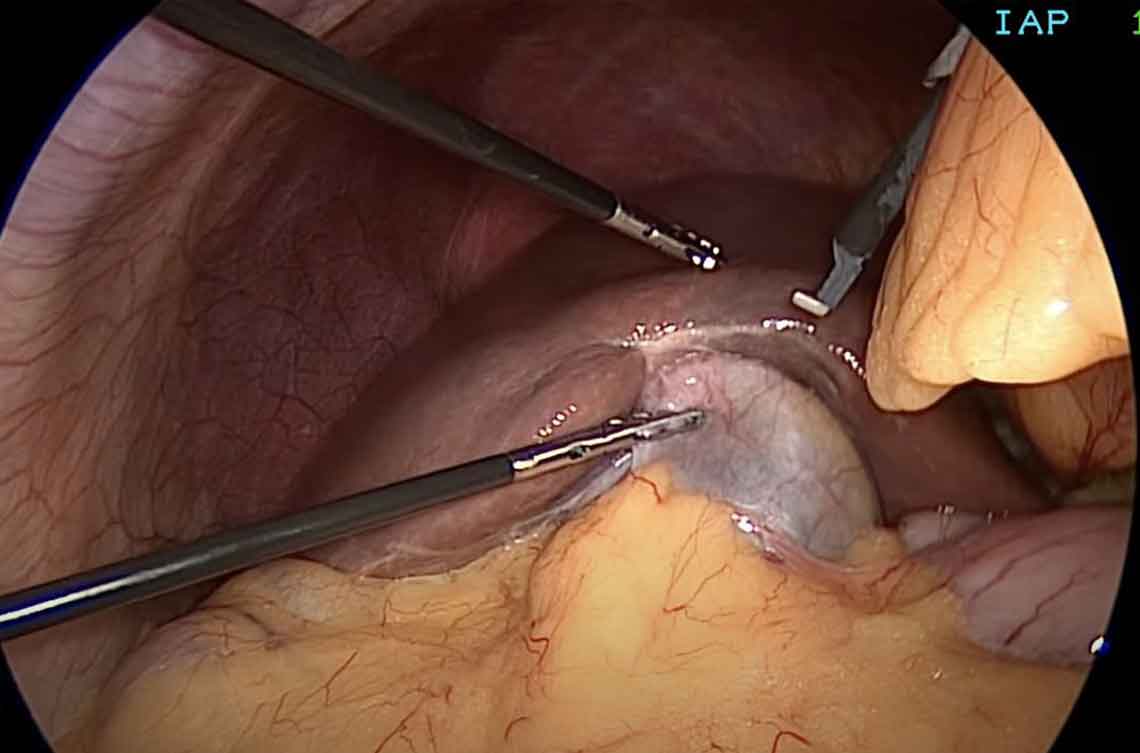

Live laparoscopic view inside abdomen during surgery

3

Operation is Performed

The surgeon uses thin instruments through the other cuts to operate — cutting, removing, or repairing — while watching the magnified live view on a big screen.